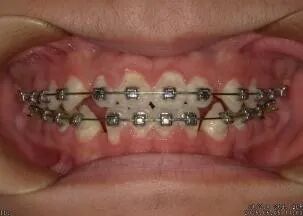

③牙列不齐清洁困难 ④牙齿矫正中和牙齿矫正后